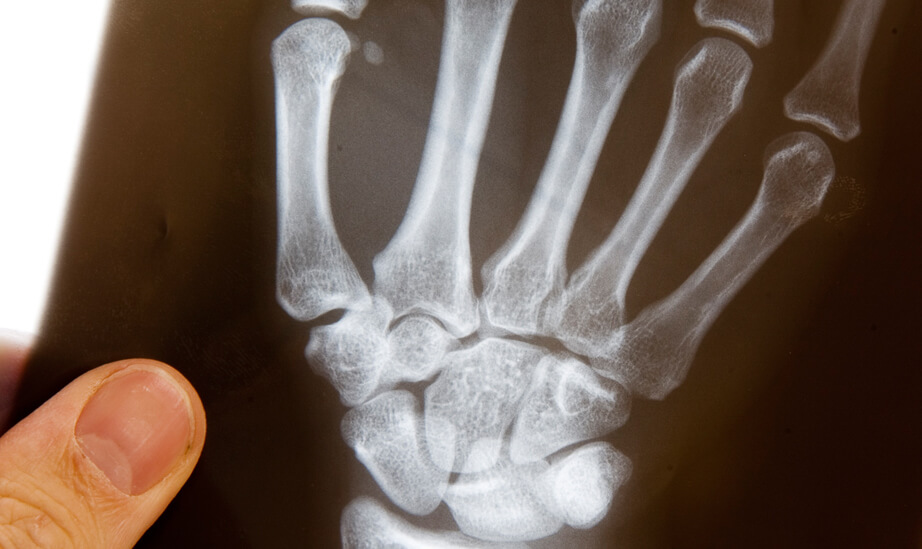

Ziel der Handrehabilitation-Therapie ist eine schnellstmögliche Wiederherstellung aller gestörten Funktionen für einen uneingeschränkten Einsatz der Hand in Alltag, Beruf und Freizeit zu erreichen. Zu den typischen Erkrankungen/Verletzungen der Hand gehören z.B.: Frakturen (Knochenbrüche), Distorsionen (Verstauchungen), Luxationen (Ausrenkungen), Nervenverletzungen, Nervenkompressionssyndrome z.B. Karpaltunnelsyndrom, Erkrankungen / Verletzungen der Sehnen, schnellender Finger (Ringbandverengung), Arthrose der Hand und Fingergelenke, Rheumatische Erkrankungen, Sportverletzungen, CRPS-Syndrom (ehemals. Morbus Sudeck), Verbrennungen, Amputationen.

In der Praxis für Ergotherapie finden unter anderem folgende Behandlungsmethoden statt: manuelle Therapie nach Cyriax/Kaltenborn, vegetative Techniken, TENS-Behandlung (transkutane elektrische Nervenstimulation), Kräftigungsübungen, Taping, Weichteiltechniken, Mobilisation nervaler Strukturen, Training der Grob- und Feinmotorik, Schröpfbehandlung, spezielle Narbenbehandlung, Spiegeltherapie, Gelenkschutzberatung, Schallwellenbehandlung und Thermische Anwendungen( z.B. Paraffinbad, heiße Rolle, Wärmebestrahlung oder Kältebehandlung).